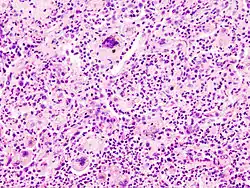

Multinucleated giant cells due to an infection. H&E stain.

A giant cell (also known as a multinucleated giant cell, or multinucleate giant cell) is a mass formed by the union of several distinct cells (usually histiocytes), often forming a granuloma.[1]